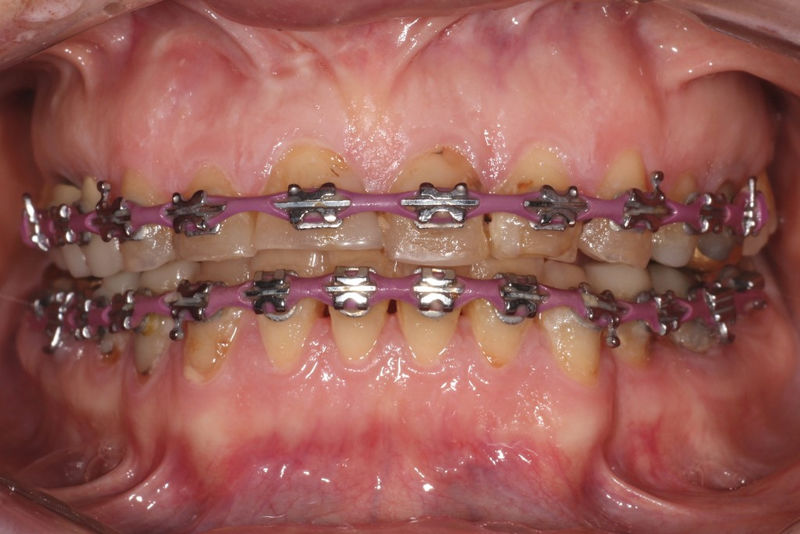

Ortodoncia y coronas.